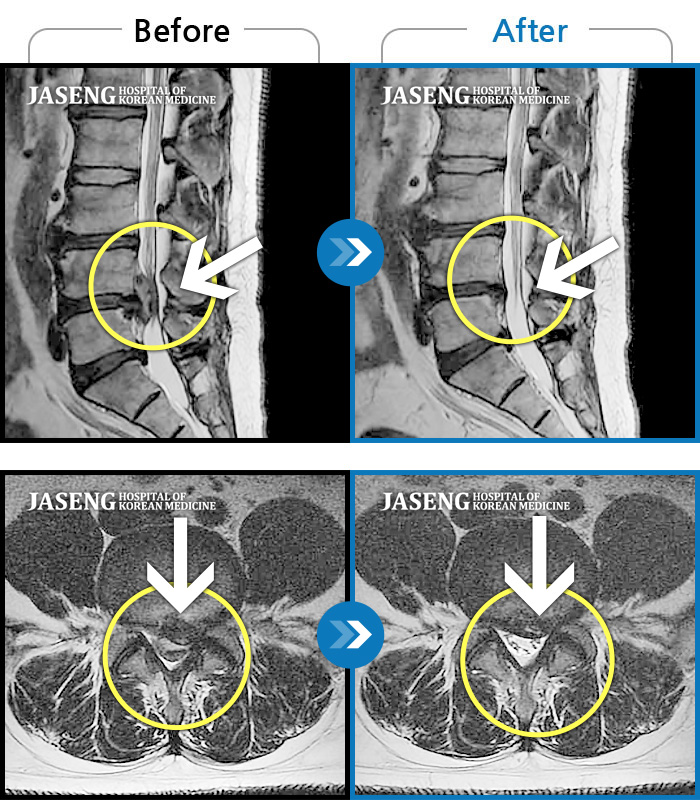

허리디스크

수원 · 김태성 원장

허리 통증과 좌측 대퇴부~종아리 저림과 통증

촬영시기

2011.03.14 ~ 2024.05.24

2024.11.21